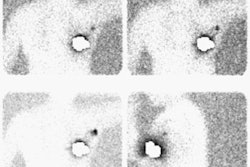

The chest CT and arteriogram on this patient are shown below. The CT demonstrates the presence of standy increased density within the mediastinal fat suggesting a mediastinal hematoma. There is also a focal change in the aortic caliber near the isthmus, and an intralumenal flap can be seen at this level (last image on top row, and first image on bottom row). Despite the CT findings, an arteriogram was performed which again demonstrated the post-traumatic aortic pseudoaneurysm.